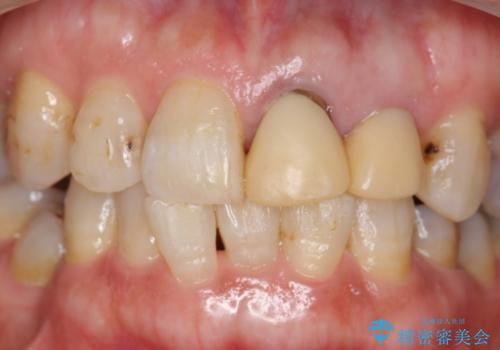

左上2抜歯後、骨および歯肉の回復を待ち、オールセラミッククラウンのブリッジによる欠損補綴を行いました。

前歯の補綴ではオールセラミッククラウンを希望される患者様が多いですが、オールセラミッククラウンの中でも、エコノミー、スタンダード、スペシャル、エクセレントとランクがあります。

その中でも特に審美性が高いのがスペシャル、エクセレントです。スペシャル、エクセレントは口腔内写真をもとに熟練の技工士が、患者様の口腔内に合わせたオーダーメイドのクラウンを製作致します。